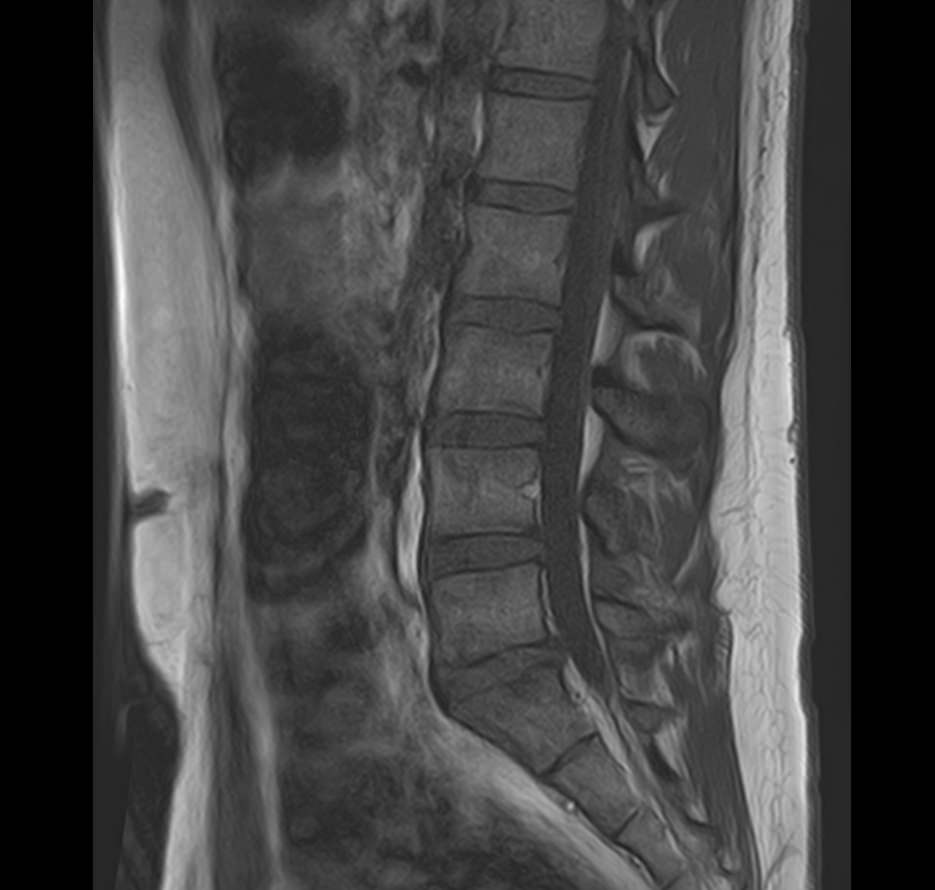

К центральной нервной системе организма относится головной мозг, расположенный в полости черепа, и спинной мозг, проходящий в спинномозговом канале позвоночного столба. В головном мозге находятся высшие центры управления всем организмом, спинной мозг имеет двусторонние связи с ними, то есть является проводником импульсов от периферии к головном мозгу и обратно.

Патология ЦНС может проявляться многообразной неврологической симптоматикой, в зависимости от уровня поражения. Причинами ее появления могут быть травматические повреждения, проникновение инфекции, демиелинизирующие и дегенеративные заболевания, сосудистая патология, опухолевые процессы.

Для диагностики заболеваний ЦНС в клинике «Доступная медицина» проводится комплексное обследование МРТ ЦНС (центральной нервной системы). Клиника укомплектована высокотехнологичным оборудованием, в частности, новейшим 32-канальным высокопольным томографом TOSHIBA VANTAGE TITAN 1,5 Тесла с высокой разрешающей способностью для точной диагностики заболеваний центральной нервной системы.

Комплексное обследование ЦНС выполняется как в стандартном режиме, когда не применяется использование контраста, так и с контрастным усилением. Для более точной диагностики некоторых патологий головного и спинного мозга внутривенно вводится контрастное вещество. С помощью контраста можно обнаружить опухолевые образования размером от 1 мм, демиелинизирующие процессы, дегенеративно-дистрофические заболевания, воспалительные процессы, сосудистую патологию.

МРТ головного и / или спинного мозга показано при диагностике повреждений, структурных отклонений или других состояний, таких как:

• грыжа, повреждение дисков позвоночника;

• планирование операций на позвоночнике, например, такой как декомпрессия сдавленного нерва.